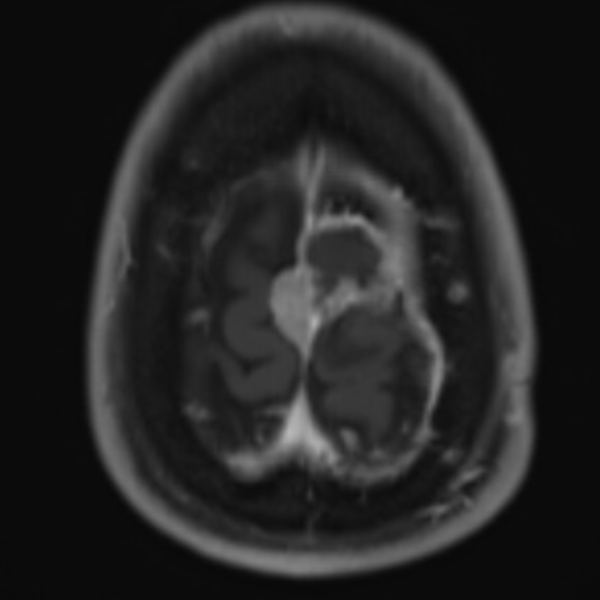

A 52 yo lady has a progression of residual disease after partial resection 5 months ago of a grade II meningioma of the falx. Unfortunately, at that time the patient did not accept treatment.

I would propose irradiating with FSRT the whole cavity and boosting with SRT the macroscopic disease. Would you share this opinion?

If not, and I suspect as much, given 5 months time to progression, then I would take the GTV and the surgical bed plus a 3 mm margin into brain tissue as CTV60/PTV60 (60 Gy in 30) then boost GTV residual +PTV with 6 Gy in 3 frx or 10 Gy in 5 frx depending what your comfortable with. Our data that will be presented and in submission suggests 66 in 33 or 70 Gy in 35 to result in better long term outcomes when residual vs 60 Gy in 30. I do sequential boost but you could SIB also. When volumes of residual are large I SIB otherwise I do the boost sequentially and a week or two gap using the Gamma Knife Icon. I would not single frx boost but fractionate the boost.